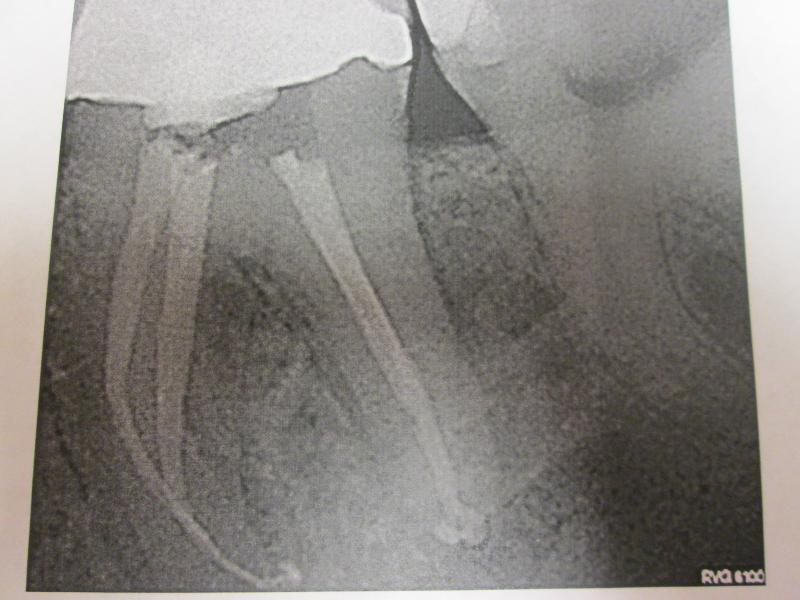

General Dentist,  Performs Root Canals ONLY - Microscope Trained Dentist

"DR. JET'S MISSION IS TO PERFORM  ROOT CANALS FOR A REDUCED FEE USING THE LATEST TECHNOLOGY  AND TECHNIQUES TO SERVICE THE MANY PEOPLE WHO ARE UNINSURED OR UNDER-INSURED GIVING EVERYONE AN OPPORTUNITY TO SAVE THEIR TOOTH!"